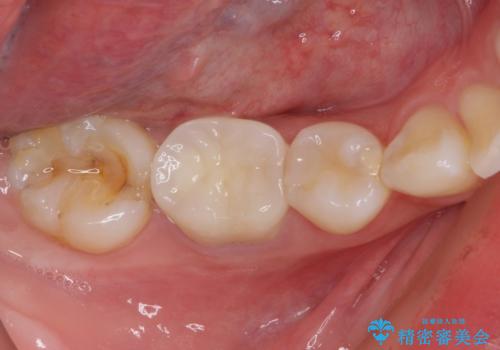

日頃の歯磨きをしっかりと行ってくださるので、新しい仮歯に変えてから速やかに歯肉の状態が改善されました。

歯肉からの出血がほとんどないため精度の良い型取りができ、非常に適合の良い補綴治療を行うことができました。